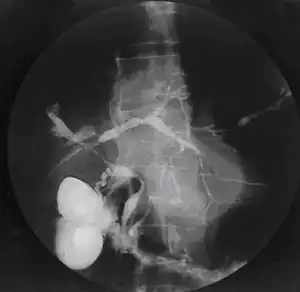

| Cholangiogram of primary sclerosing cholangitis | |

Historically, a cholangiogram would be obtained via endoscopic retrograde cholangiopancreatography (ERCP), which typically reveals "beading" (alternating strictures and dilation) of the bile ducts inside and/or outside the liver. Currently, the preferred option for diagnostic cholangiography, given its noninvasive yet highly accurate nature, is magnetic resonance cholangiopancreatography (MRCP), a magnetic resonance imaging technique. MRCP has unique strengths, including high spatial resolution, and can even be used to visualize the biliary tract of small animal models of PSC.[19]